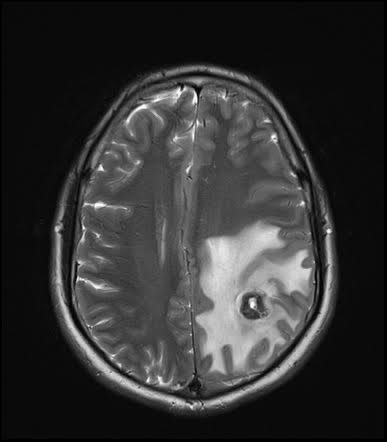

Issue 1: Neurocysticercosis The image is an MRI scan of a patient with neurocysticercosis which was sourced from radiopaedia.org. The patient is a 20 year old male. Now let’s dig into symptoms and how can one face this issue. Symptoms: • seizures: due to irritation in

Issue 1: Neurocysticercosis

The image is an MRI scan of a patient with neurocysticercosis which was sourced from radiopaedia.org. The patient is a 20 year old male.

Now let’s dig into symptoms and how can one face this issue.

Symptoms:

• seizures: due to irritation in